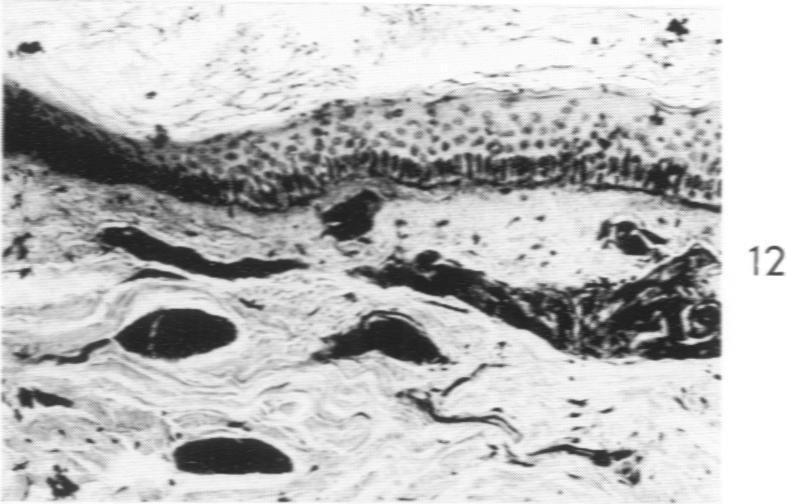

Lipoid Proteinosis (Lipoglycoproteinosis): A Histochemical Study of Two Cases.

Am J Pathol. 1962 May;40(5):599-613.